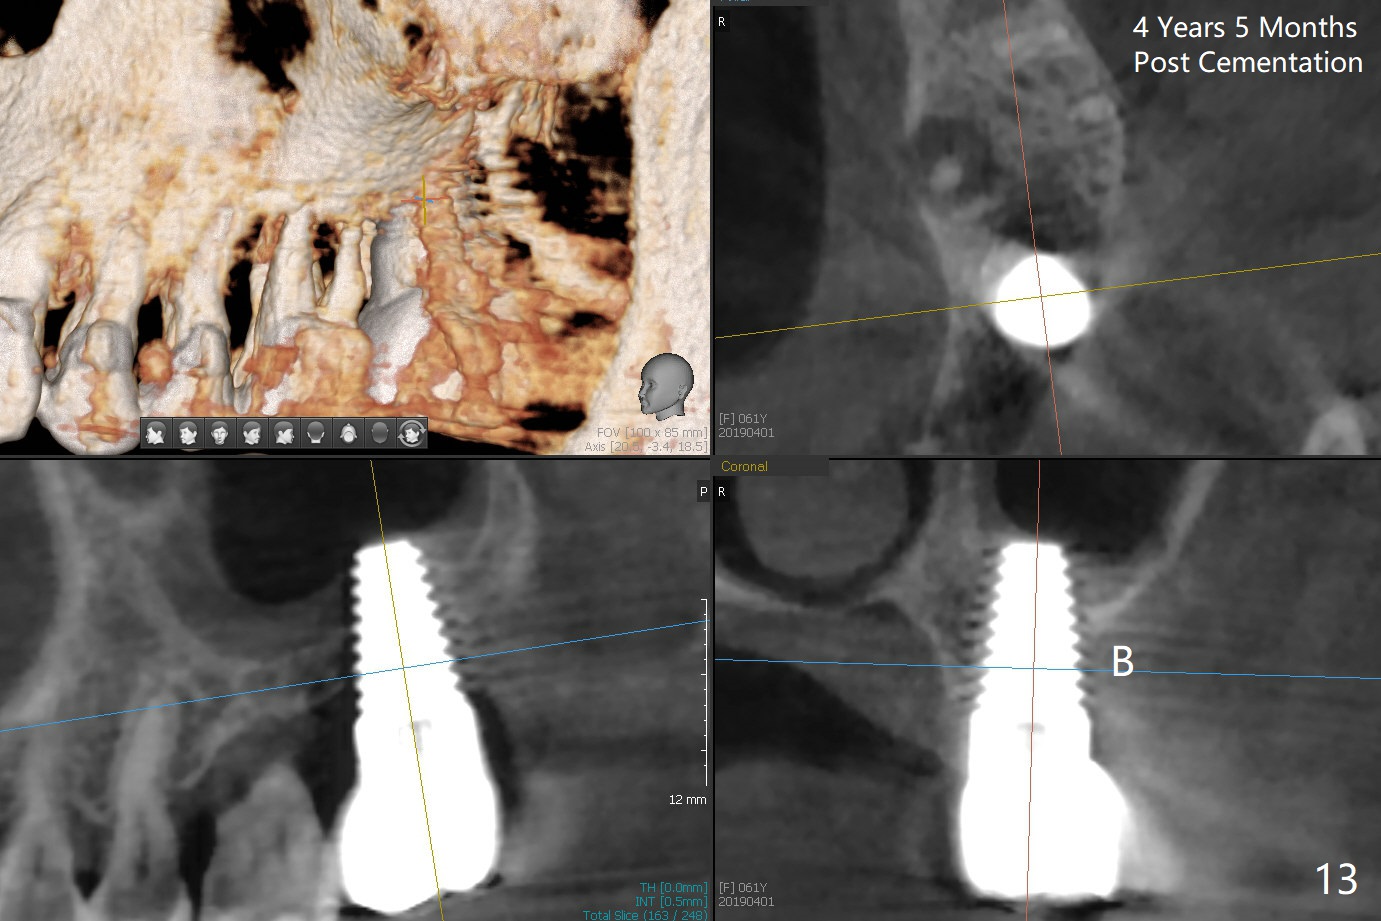

Gingival Recession

A 56-year-old female has recurrent infection and buccal gingival recession (Fig.1 *) after root canal therapy in the upper left 2nd molar (Fig.2). The extraction socket is single and large. Osteotomy forms by using a series of osteotomes (2-5 mm in diameter) mesiopalatal to the center of the socket. The sinus floor is thin (approximately 2-3 mm). The osteotomy is further enlarged by inserting 4.5-8 mm taps at the depth between 14 and 17 mm from the gingival margin. The last tap has barely achieved stability (Fig.3). It appears that the tap has almost obliterated the socket. Allograft is pushed into the sinus before placement of a 8x17 mm implant. The insertion torque is between 15 and 20 Ncm (Fig.4). The gingiva-level implant is slightly subgingival except buccal (Fig.5). To facilitate buccal gingival re-growth and cover the exposed implant surface, bone graft is placed subgingival (Fig.5 ^). The gingival sulcus is closed partially by placement of a thin strip of collagen membrane (not shown). The wound is protected by applying perio dressing.

Next time she returns 4.5 months postop, bone looks normal around the implant (Fig.7), whereas the buccal gingival recession appears to get worse with 1-2 implant thread exposure (Fig.8 >). To avoid this complication, the initial osteotomy should be placed as palatal as possible; when the implant is placed with gingival recession (Fig.5), soft tissue graft should be performed. The implant should be smaller.

Model study shows that the implant is placed distally (Fig.9,11) in addition to buccal implant exposure (Fig.10 arrowheads). Postop, the patient complains of upper left discomfort, which is more likely associated with furcal infection of the tooth #14. The symptom disappears after use of water pik. Panoramic X-ray is taken 6 months post cementation (Fig.12).